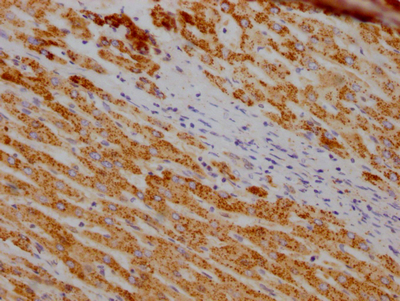

IHC image of CSB-RA633872A0HU diluted at 1:100 and staining in paraffin-embedded human liver cancer performed on a Leica BondTM system. After dewaxing and hydration, antigen retrieval was mediated by high pressure in a citrate buffer (pH 6.0). Section was blocked with 10% normal goat serum 30min at RT. Then primary antibody (1% BSA) was incubated at 4℃ overnight. The primary is detected by a Goat anti-rabbit IgG polymer labeled by HRP and visualized using 0.05% DAB.